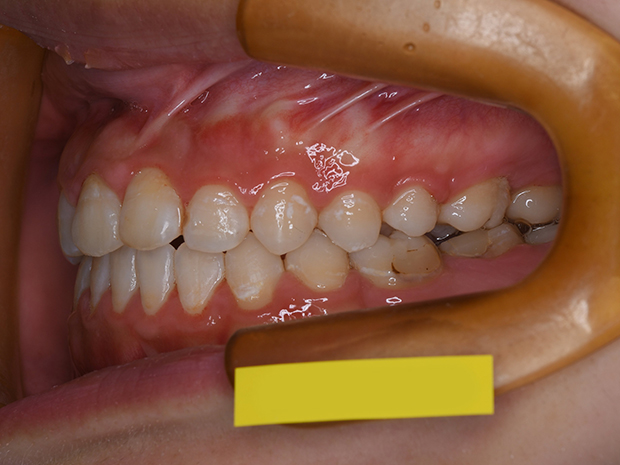

【ハーフリンガル】叢生 抜歯 上顎舌側マルチブラケット装置

| 主訴 |

ガタガタ |

||

|---|---|---|---|

| 診断名 |

右側Angle II級叢生 |

||

| 年齢 | 19歳 | 性別 | 女性 |

| 治療に用 いた装置 |

ハーフリンガル装置 (セミカスタム) | 抜歯部位 | 上顎両側第一小臼歯 下顎両側第二小臼歯 |

| 治療期間 ・回数 |

2年・24回 | 治療費 概算 |

約85万円 (調整料を含む) |

| 治療内容 詳細 |

歯科衛生科に入学し、自分の歯ならびが気になり始めたとのこと。上の歯列のみ舌側矯正(裏側矯正)、下は表側の、ハーフリンガルで治療を行いました。 |

||

| リスク・ 副作用 |

装置による違和感。疼痛、歯根吸収など |

||